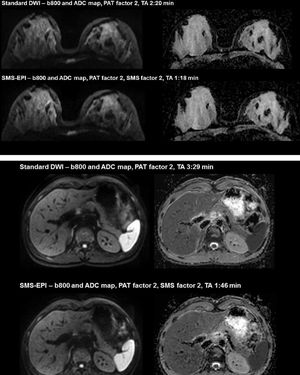

Diffusion-weighted imaging (DWI) has great potential in body oncology, however, being a single-shot technology, the acquisition is relatively time consuming. Simultaneous Multi-Slice (SMS)-EPI deploys multiband pulses to excite multiple slices simultaneously. This excitation is combined with a blipped CAIPIRINHA approach during readout to reduce g-factor related SNR loss. As a result, an additional acquisition time reduction of up to 46% without compromising image quality compared to a standard GRAPPA 2 can be achieved with SMS 2 in combination with GRAPPA 2 in breast and abdominal scans. Prerequisite: Software version syngo MR E11C and SMS-EPI license.